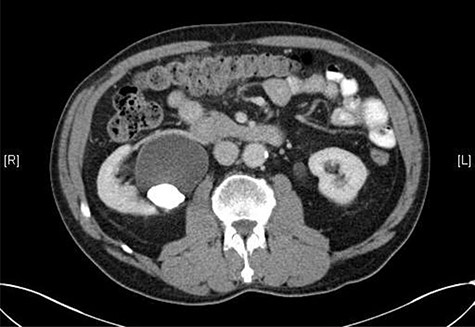

Seven months after the patient’s initial presentation, they underwent a laparoscopic right hemicolectomy; intra-operatively, a 6Ch/24 cm stent was inserted into the right ureter by the colorectal surgeon who had good experience of ureteric stent placement. The position of the stent was confirmed with cystoscopy and retrograde pyeloureterogram (Fig. 2).

Retrograde pyeloureterogram confirming position of right ureteric stent.